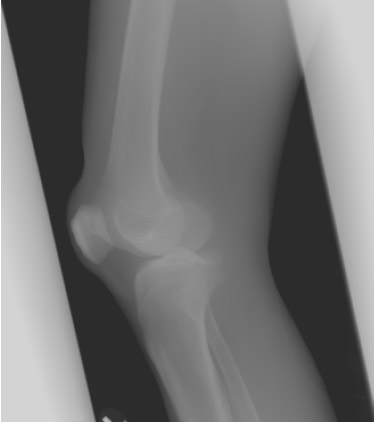

Pretest Radiographic Evaluations: The following pictures illustrate examples of the radiographic views utilized for the LEAP 99-2 study. These are examples of normal specimens taken before testing.

Picture 5 Lateral Knee

Picture 6 AP Leg